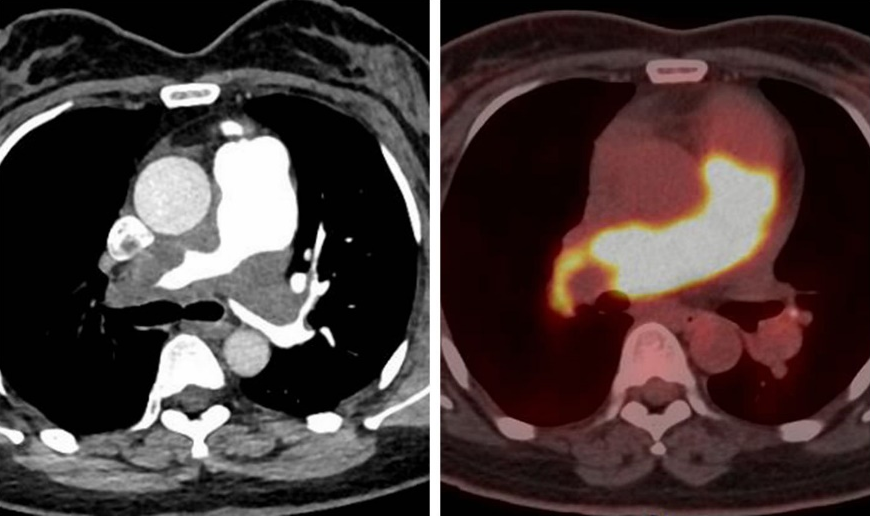

患者为44岁女性,因胸闷、咳嗽4月余来院就诊,此前在当地医院诊断为肺动脉栓塞,治疗效果欠佳。患者入院后,心内科专家仔细回顾患者病史,结合临床表现及影像学资料,对肺动脉内占位病变进行鉴别诊断,认为肺栓塞诊断不成立,随后组织多学科会诊,最终通过PET/CT检查明确了诊断方向——肺动脉恶性肿瘤。病理的取得对患者的诊断治疗至关重要,心内科肺血管亚专业团队与患者及家属沟通后,决定行经导管肺动脉活检术获取肺动脉占位组织。